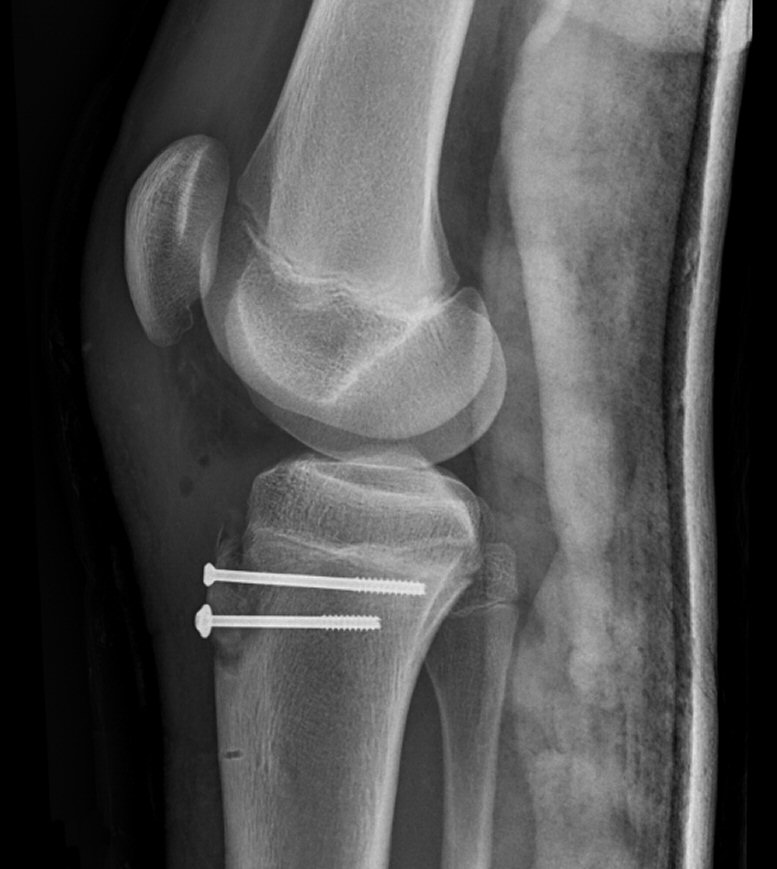

Avulsion av processus tibiae, fixerad med två skruvar.